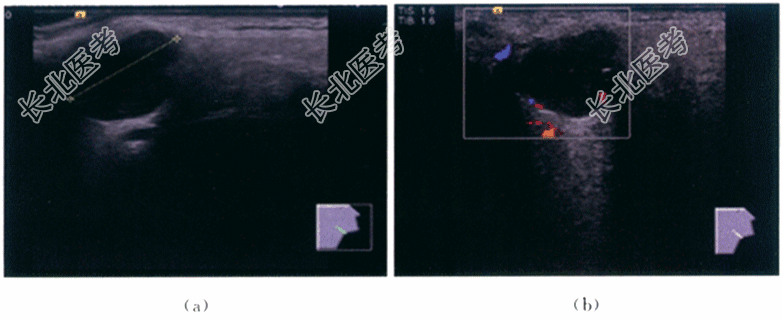

- [材料题] 患者,男性,41岁,因"发现右侧颌面部肿块2月"就诊。患者于2月前无意发现右侧颌面部肿块,无疼痛不适,无吞咽困难,无声嘶,无呼吸困难,无发热。否认上呼吸道感染病史,肿块大小无明显变化。体格检查:患者右侧腮腺区可触及约1cm×2cm肿块,质软,无压痛,边界清,活动度可,未闻及血管杂音。实验室检查无殊。影像资料如下:

- 简答题1、该患者的超声诊断是什么?

- 简答题2、该疾病超声诊断的详细特征是什么?